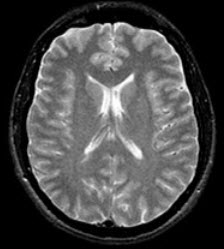

患者,男,30岁,头痛、呕吐三周,低热,脑膜刺激征(+),MRI如图,最可能的诊断是( )

A:结核性脑膜炎

B:真菌性脑膜炎

C:朊病毒感染所致脑损害

D:HIV病毒感染脑损害

E:巨细胞病毒感染脑损害